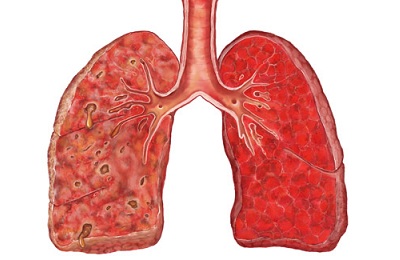

Внутрибольничная пневмония клинически отличается тяжелым течением. Диагноз госпитальной пневмонии устанавливается на основании легочных и внелегочных проявлений, которые являются признаками поражения легких и интоксикации организма:

-

Легочные проявления: кашель, мокрота (отсутствие или обильное выделение гнойной мокроты), боли в грудной клетке, выраженная одышка, учащенное и поверхностное дыхание.

Присутствуют физикальные признаки, такие как: укорочение (притупление) перкуторного звука, бронхиальное дыхание, влажные хрипы, крепитация при прослушивании фонендоскопом области воспаления, шум трения плевры, выделение большого количества мокроты с большим количеством гноя.

- Внелегочные проявления: повышение температуры тела до 38,5°С и выше, общая слабость, потливость, головные боли, нарушение сознания, ухудшение аппетита.